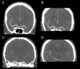

Arterial branch occlusion

Central retinal artery occlusion (CRAO) is a disease of the eye where the flow of blood through the central retinal artery is blocked (occluded). There are several different causes of this occlusion; the most common is carotid artery atherosclerosis. [Source: Wikipedia ]